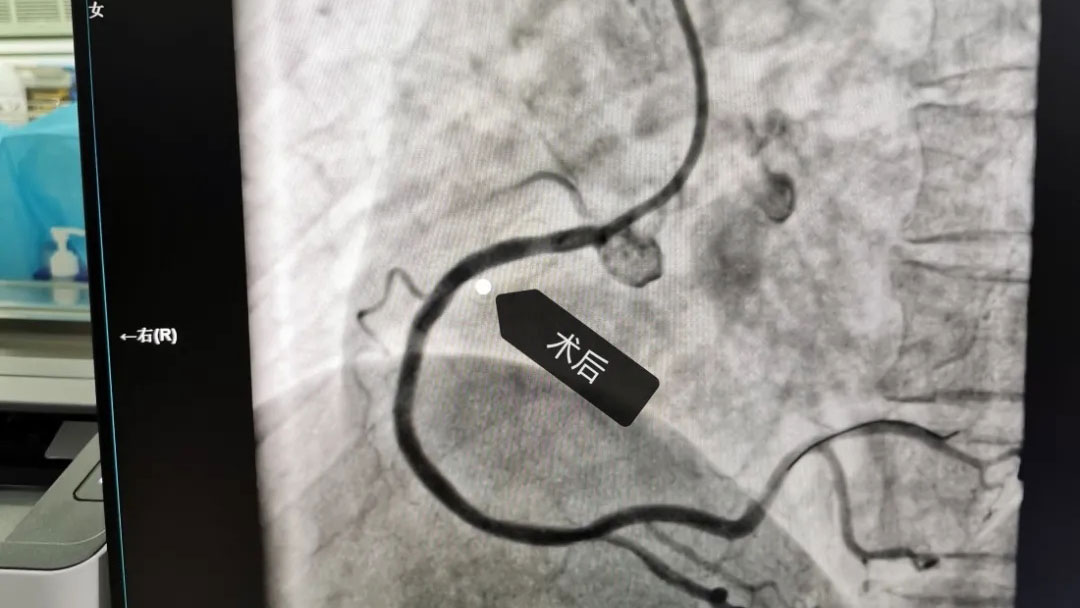

此次赠送锦旗的周某,为本周冠状动脉造影术后的患者,深深感受到术前术中术后带来的快捷和方便,7月14日,周某携其家属为感谢武汉亚心总医院王琛主任及来凤县中心医院心内科团队,专程送来了一面锦旗,以示感谢。

据了解,来凤县中心医院常规开展冠状动脉造影及冠脉支架植入术以来,极大提高了冠心病的诊疗水平,而且还常规开展远桡动脉穿刺,大大改善近端桡动脉穿刺带来的“肿、胀、痛”等术后不适。取得了良好的诊断和治疗效果,赢得了广大病患者的赞誉。